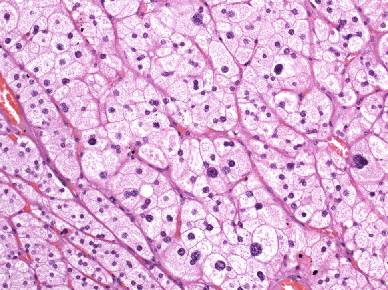

Histologically, the adrenal gland can be divided into the medulla, which shows a relatively homogeneous structure and the cortex with three concentric zones (zonae glomerulosa, fasciculata and reticularis). Due to their different embryologic origins, the cortex and medulla produce different hormones. While catecholamines are synthesized in the medulla, steroid hormones, such as mineralocorticoids, glucocorticoids and sex steroids are synthesized in the zonae glomerulosa, fasciculata and reticularis of the cortex, respectively, with an overlap in hormones synthesized by the zonae fasciculata and reticularis. Our patient’s adenoma showed enlarged cells with pale cytoplasm and centrally placed nuclei with marked variation in size and there were also binucleated cells but no mitotic figures (Fig. 1).

Fig. 1

Typical adrenocortical adenoma composed of large cells with abundant foamy cytoplasm and distinct cell borders. Note coarse nuclear chromatin, variation in nuclear size and occasional binucleated cells but no mitotic figures (H&E, ×100)